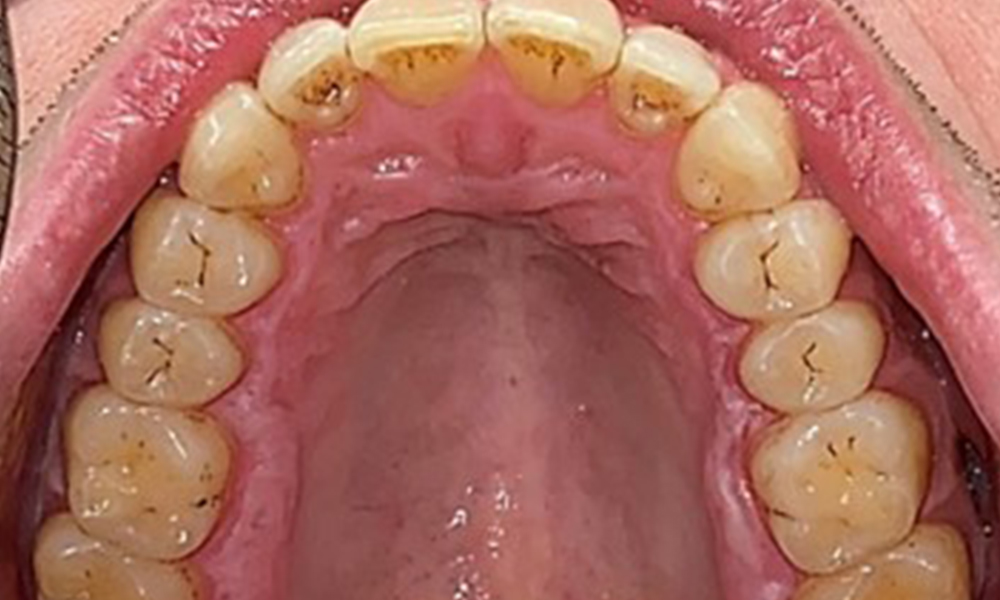

Frontal view

Fig. 2 Frontal view, © Dr R. Krapf

Extraoral and intraoral findings

There were no pathological extraoral findings. During intraoral examination, inspection of the frontal view revealed brownish discolouration near the keratinised gingiva and at the transition to the moveable mucosa (Fig. 2), which could be attributed to nicotine consumption. Whitish mucosal lesions were observed on the palate, particularly near the maxillary molar palatal surfaces, indicating increased keratinisation and can also be attributed to nicotine consumption. The tongue was covered with a removable white and brownish coating.